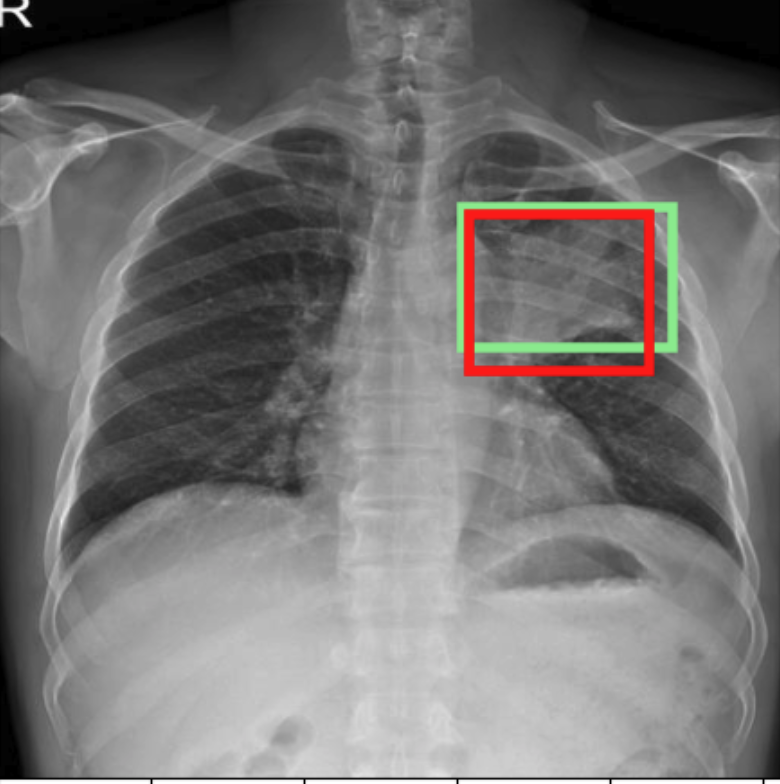

4.3.3 Visual grounding

In this section, we evaluate RadVLM’s visual grounding capabilities, which could help clinicians localize specific regions or pathologies on a CXR. This is particularly useful once a pathology has already been identified – either by a radiologist’s input or through our previously described AI tasks – since it allows one to pinpoint exactly where the abnormality appears on the image.

We report performance metrics for the three main grounding tasks RadVLM was trained on: anatomical grounding using the Chest Imagenome test set, abnormality grounding using the VinDr-CXR test set, and phrase grounding using the MS-CXR test set (Table 1). For each task, we use mean Average Precision (mAP) as our primary evaluation metric.

Our results show that RadVLM performs well at localizing anatomical regions (e.g., “right lung”, “aortic arch”, illustrated in Figure 5a), achieving a mAP of 85.8 %, by far surpassing the other CXR grounding models (Table 4). This advantage is partly explained by including the Chest Imagenome dataset (and thus the anatomical grounding task) in the training set, which CheXagent and MAIRA-2 did not leverage. However, it remains a key feature for any grounding model to possess a fine-grained understanding of CXR anatomy.

For the abnormality grounding task, RadVLM is less consistent (Figure 5b), likely due to higher sparsity of abnormality locations and labels, yet it still achieves best performance (Table 4). For the phrase grounding task, while MAIRA-2 and CheXagent demonstrate great performance, RadVLM surpasses them with a mAP of 81.8% (Table 4), presumably benefiting from the newly released PadChest-GR dataset (Castro et al.,, 2024) used for training.

Overall, these results show that our instruction tuning strategy for visual grounding (covering three essential tasks), combined to a modern VLM backbone, offers a promising avenue to help clinicians localize anatomical and pathological features during a CXR exam. Furthermore, providing fine-grained details within an LLM-generated output may also enhance the ability to answer grounded questions in a multi-turn setting, as we explore next.

a. Anatomical grounding

silhouette

junction

structures

lung

abdomen

mediastinum

arch

b. Abnormality grounding

thickening

fibrosis

enlargement

lung disease